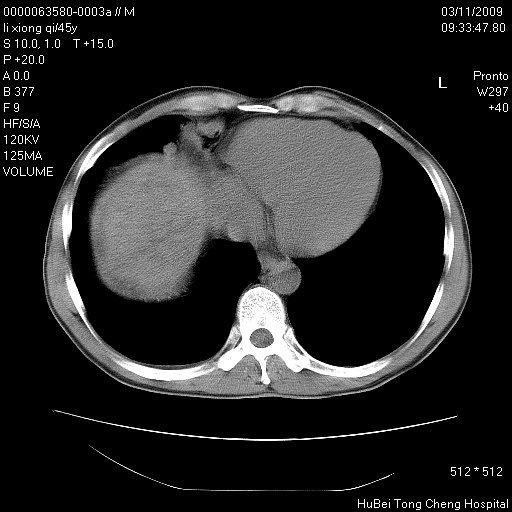

患者 男,45岁。胸痛,咳嗽伴痰中带血1月余。

临床诊断:肺结核?

胸部ct轴位平扫(层厚10mm,螺距1.5,重建间隔10mm),图像如下:

考虑肝癌肺转移